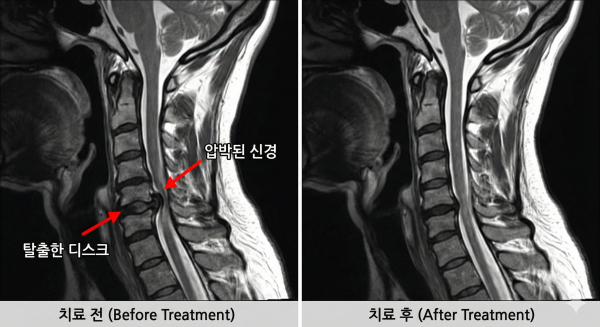

이런 압박이 지속되면 디스크가 탈출하거나 통증이 발생하며,

신경이 눌려 팔과 어깨가 떨어져 나갈 듯한 통증을 느끼게 됩니다.

보존적 치료로 호전되지 않는 심한 협착층이나 디스크의 경우,

경추내시경감압술이 효과적인 대안이 됩니다.

이 치료법은 약 1cm 미만의 최소 절개를 통해 내시경으로 병변 부위만 정밀하게 제거합니다.